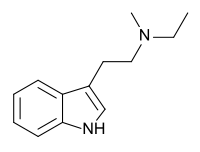

| NET | artificial | H | H | CH2CH3 | N-ethyltryptamine | 61-53-0 |

| MET | artificial | H | CH3 | CH2CH3 | N-Methyl-N-ethyltryptamine | 5599-69-9 |